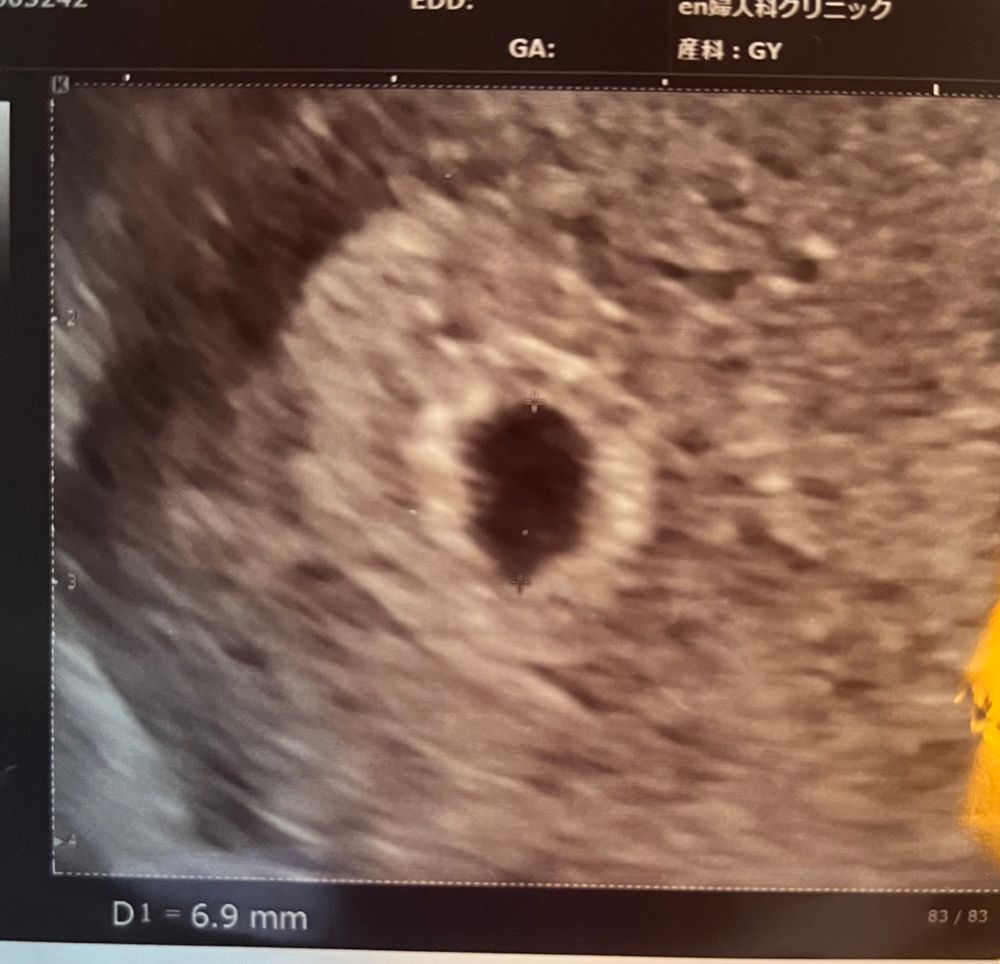

Вот у меня точно такое было как у вас и кровь розовая была, на 24 дпп уже открылось кровотечение по ногам текло, у нас тоже в Канаде не сохраняют! Я лежала , были две пластинки транексама, пила их, на узи был тонус тоже сплюснуло пя, и вот такое кровавые сгустки были возле пя, врач сказала что кровать будет пока не выйдет это все, в итоге кровило до 10 недель

Плодовое яйцо сплющено норма. Если врач сказал, что гематома, да она либо выйдет сгустком коричневым, либо коричневыми выделениями помажет. Появится алая кровь, срочно к врачу. Главное сердечко бьется! Легкой беременности вам!

Ксения, у меня вообще не мажет, только алой кровью льет по 2-4 чайной ложке. Поэтому я сильно тревогу била. Врач не сказала, что именно кровит, вот и пытаюсь понять по снимку узи🤔.